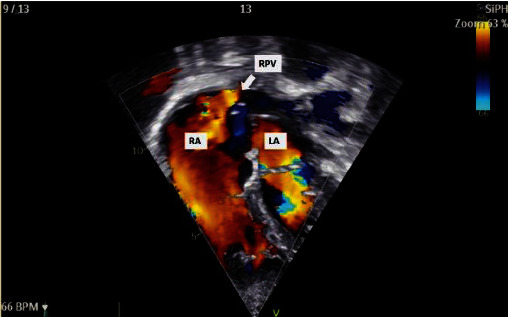

下静脉窦缺损(SVD)较上静脉窦缺损少见。缺损的下缘横跨下腔静脉口,这使得通过双腔静脉插管进行手术修复成为一项技术挑战。无顶右肺静脉的开口是由静脉窦缺陷的房间交通引起的,导致部分肺静脉异常引流(PAPVD)。最近报道了一种新型经导管闭合上位SVD;然而,经导管关闭下位SVD尚未在已发表的文献中报道。在这里,我们报告了首例成功的经导管关闭下静脉曲张,使用裸露和覆盖支架,并将PAPVD重新定向到左心房,以避免肝静脉闭塞。在这一单例报告中,我们仔细地描述了计划过程,手术是如何进行的,以及重新捕获和重新定位迁移支架所采取的步骤。在手术前和手术过程中,仔细选择患者并对肺和肝静脉解剖进行深入评估是取得成功的必要条件。

Inferior sinus venosus defect (SVD) is less common than a superior one. The lower edge of the defect straddles the orifice of the inferior vena cava, and this makes surgical repair via bicaval cannulation a technical challenge. The orifice of the unroofed right pulmonary vein is caused by the interatrial communication in sinus venosus defects which results in partial anomalous pulmonary vein drainage (PAPVD). Novel transcatheter closure of a superior SVD has recently been described; however, transcatheter closure of an inferior SVD has not yet been reported in the published literature. Here, we report the first successful transcatheter closure of an inferior SVD with bare and covered stents and the rerouting of a PAPVD into the left atrium to avoid occlusion of the hepatic veins. In this single-case report, we carefully describe the planning process, how the procedure was performed, and the steps taken to recapture and reposition a migrated stent. Careful patient selection and intensive assessment of pulmonary and hepatic vein anatomy before and during the procedure were necessary to achieve a successful outcome.